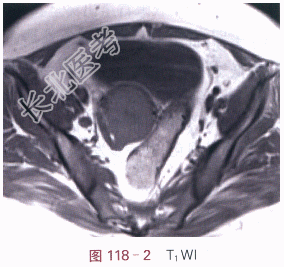

影像学资料如图118-1~图118-4所示。

读片分析:宫颈见内生型肿块,自宫颈外口向颈管内生长,侵犯宫颈深部组织,宫旁组织未受累,T₁WI呈等信号,T₂WI稍高信号,信号较均匀;增强后,瘤体强化较明显、欠均匀,但低于邻近正常的子宫。